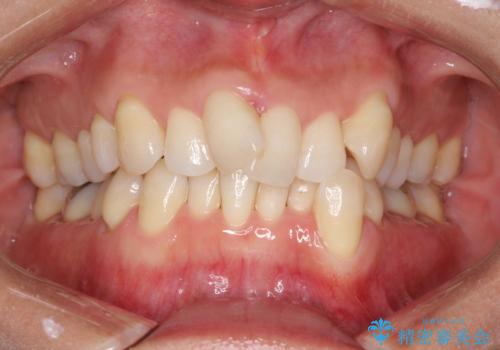

前歯のデコボコ インビザラインによる目立たない矯正

- 前歯のデコボコを主訴に来院された患者様です。

目立たないそうちをご希望されたので、インビザラインにて治療することとしました。

歯と歯の間をわずかに削ってスペースをつくり、デコボコを改善しました。